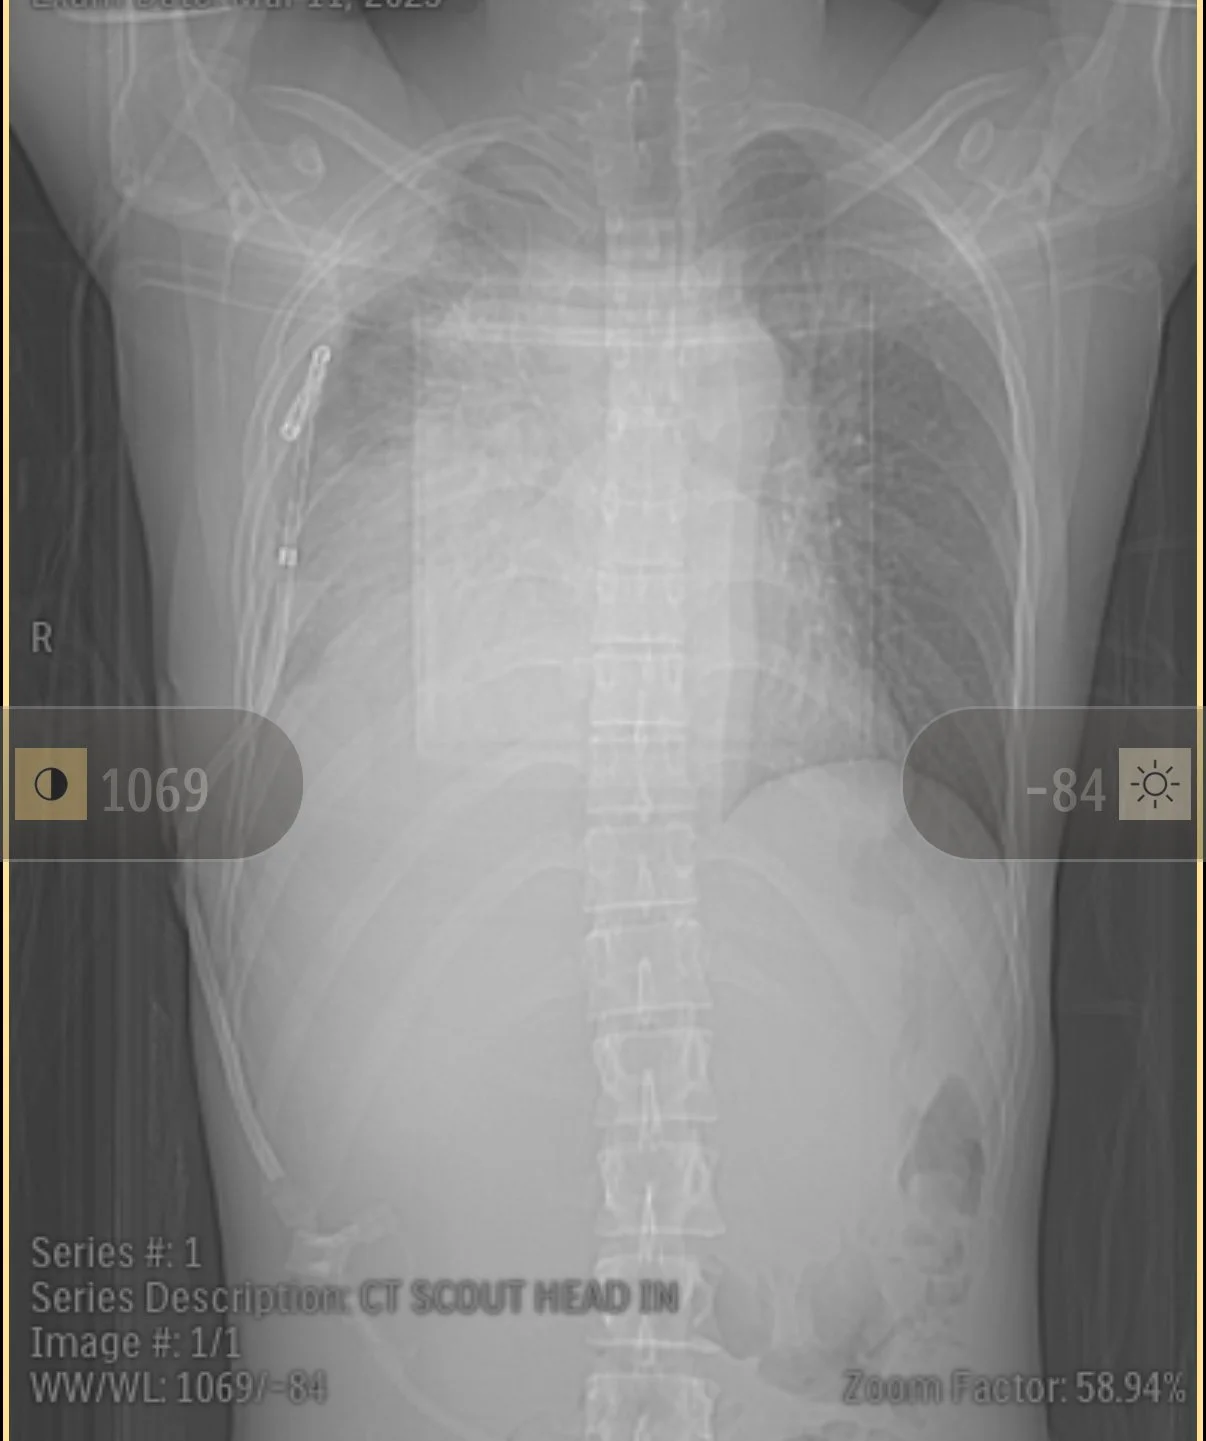

Back in mid-April I had a second PET scan to check on the lymphoma mass in my chest and make sure there was no evidence of disease spreading. When I had my first PET scan at the end of my first cycle of treatment, the mass measured 11 x 16.5 cm. My oncologist, Dr. Bair said it was the largest lymphoma mass of this type he had ever seen. Well, friends, after my second cycle, the mass had shrunk to 3 x 7 cm!! A huge difference and a vast improvement in the disease burden on my body.

My first PET scan. All of the cloudiness in the center of my chest is lymphoma mass.

My second PET scan. Lots more room for my lungs and heart to do their thing!